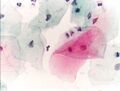

صورة مجهرية لاختبار عنق الرحم تُظهر آفة داخل الظهارة منخفضة الدرجة (LSIL) ومخاطية باطن عنق الرحم الحميد. صبغة عنق الرحم .